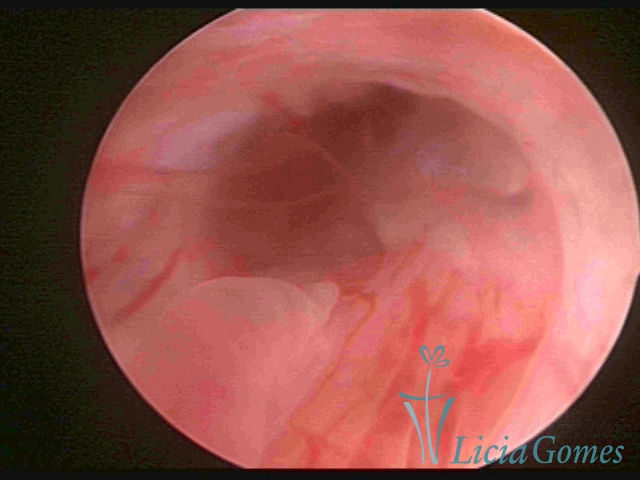

PÓLIPOS ENDOCERVICAIS

São tumores benignos, resultantes da proliferação focal reativa aos processos inflamatórios ou à situações de hiperestrogenismo, e podem ter sésseis (com a base de implantação larga) ou pediculados do epitélio.